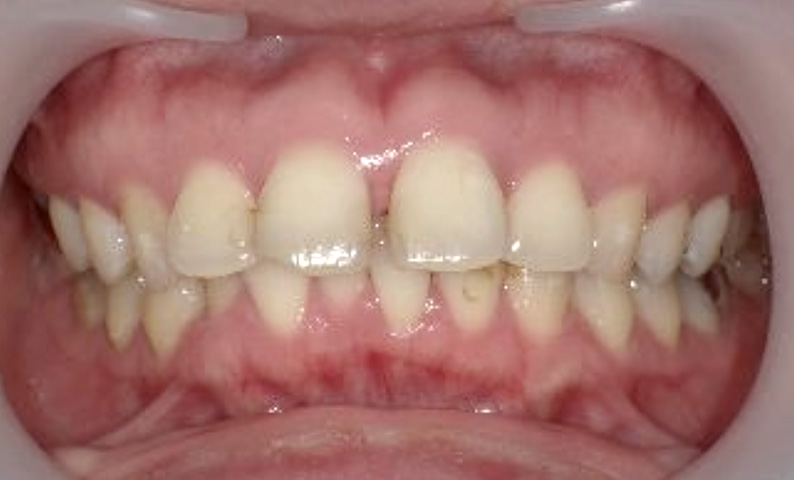

症例_004 下顎だけの部分矯正

治療期間:7ヶ月金額:24万円+税男性前歯のガタガタ下の前歯だけ

| Before | After |